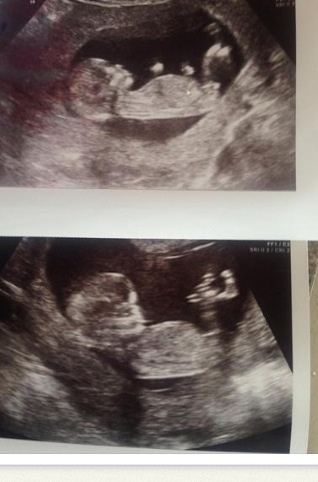

I was just wanting to know if you could have a guess at ye gender of my baby please :)

Ill post the few scan pics I have

I'm 13+2

Last pic shows the most visible nub. I'd say def a girl, considering you're beyond 13 weeks.

If you were earlier, I'd have said boy. But given you are beyond 13 weeks, I think we would see more rise if it were a boy. So I tentatively lean girl.

Pink but I agree with above. If you weren't at 13 weeks I would have thought the nub was on the rise.